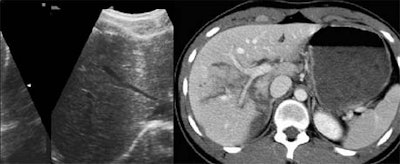

![]() |

"Ultrasound was very sensitive and specific [for detecting] free fluid when compared with CT results. However, it was very poor for showing parenchymal injuries... Twenty-five percent of the patients had visceral injuries with no associated free fluid," Poletti said. "Therefore, ultrasound is limited by the high amount of organ injuries that are not associated with free fluid."